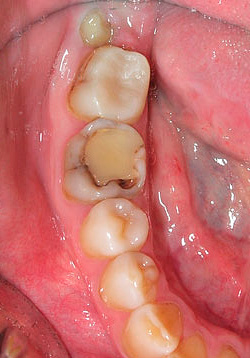

La foto sotto mostra un dente in cui sono visibili profonde cavità cariate interne sotto una luce intensa: